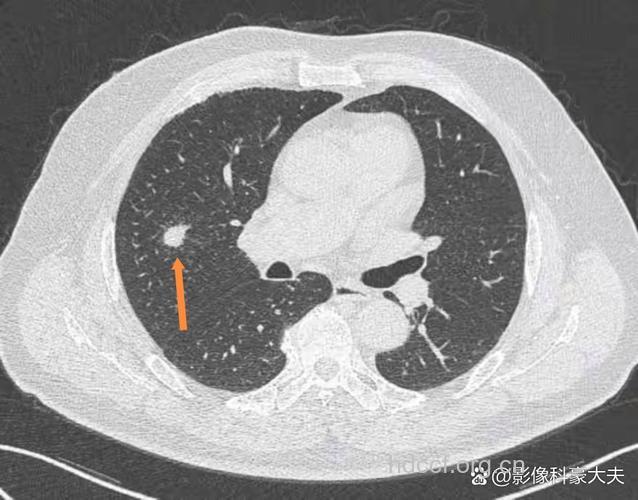

董金狮表示,一次性筷子在制作过程中不可能做到无菌,而木材、竹子又含有水分,很容易发霉。 而且,一次性筷子的保质期只有半年,消费者长期使用过期的一次性筷子,霉菌就可能进入肺部,因为霉菌在潮湿的环境中容易繁殖,这就容易导致消费者患肺病,例如肺结核、肺癌。 如果消费者一定要使用一次性筷子,董金狮建议,使用前用开水烫一下,这样可以清除它表面的灰尘,杀死一些细菌,去掉一次性筷子表面的有毒化学物质。